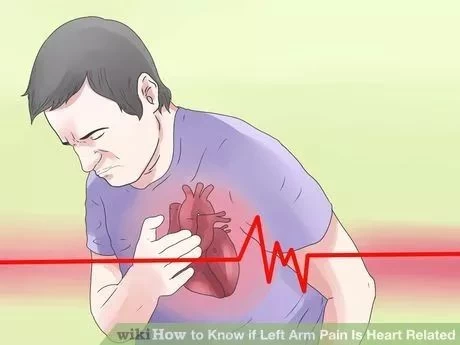

قلب یکی از مهم ترین اعضای بدن است که وظیفه انتقال خون به انواع اعضای بدن را دارد. میتوانید تصور کنید اگر قلب کار نکند چه اتفاقی می افتد؟ در این پست ما به انواع ناراحتی قلبی، علائم آنها، چگونگی رفتار با شخصی که ناراحتی قلبی دارد و اینکه ناراحتی قلبی چه هست می پردازیم. پس تا آخر با من همراه باشید!